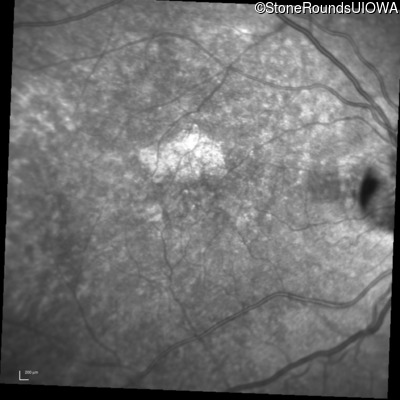

Blue Autofluorescence - Right - 20/32 +2

Exemplar